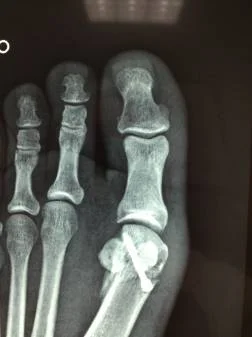

Radiografía postoperatoria

Paciente femenino de 32 años, portadora de hallux valgus doloroso en el pie derecho. Intervenida quirúrgicamente por el Dr Alberto Martínez Conde, practicandole cura operatoria con osteotomia del primer metatarso según técnica de Chevron y fijación con tornillo de Bold de 3.0 mm.